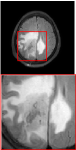

Figure 5 provides the qualitative comparison of the various methods on the four datasets at a scale of 4. The top, second, third, and bottom rows are the SR results under the FastMRI, clinical brain, clinical tumor and clinical pelvic datasets, respectively. The red boxes indicate the zoom-in region of complicated anatomical structures along with their corresponding error maps. Note that the brighter textures in the error maps, the lower the quality of the reconstructed images. As can be seen, compared to methods based on Transformers and CNNs, diffusion-based methods like DisC-Diff and DiffMSR (Ours) are capable of reconstructing high-realistic images with promising reconstruction metric scores (PSNR and SSIM). Nevertheless, while DisC-Diff can reconstruct high-precision MR images, it does not preserve the structure present in the original HR images, introducing some additional information that can affect medical diagnosis. In contrast, our method combines DM and PLWformer, which can preserve the original image’s structure while restoring high-frequency information.

In this section, we present more visual qualitative comparisons. Figures 8, 9, 10, and 11 show the reconstruction results of each method in FastMRI, clinical brain, clinical tumor, and clinical pelvic, respectively. As can be seen, although DisC-Diff can reconstruct MR images with high-frequency information, it fails to preserve the structure and content of the original Target HR image effectively, resulting in image distortion. In contrast, our proposed DiffMSR can restore high-frequency information while preserving the structure of the original HR image, indicating the effectiveness of the joint use of DM and PLWformer.